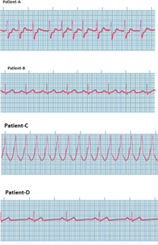

1. The four dysrhythmias ECGs are given below. Which of the following can lead to development of embolic stroke?

1. Based on the provided ECG readings, for which patient is likely to be on digoxin?

1. Patient A

2. Patient B

3. Patient C

4. Patient D